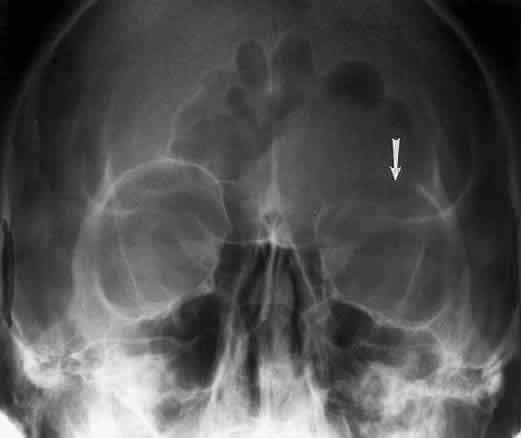

CALDWELL PROJECTION

In 1918 the evaluation of the frontal and ethmoid sinuses prompted Caldwell9 to describe a projection (Fig. 3) that eliminates the superimposition of the sphenoid bone on these paranasal sinuses. The patient is positioned with both the nose and forehead against the x-ray cassette while the x-ray beam is directed downward 15 degrees to 23 degrees to the canthomeatal line.5,6,9 This orientation also projects the petrous bones inferior to the orbit, thus avoiding obscuration of the orbital structures. As in the Waters view, the Caldwell view is a posterior-anterior projection. This excellent view of the frontal and ethmoid sinuses also allows good visualization of the orbital rims, greater and lesser sphenoid wings, lacrimal gland fossa, medial orbital wall, and both the superior and inferior orbital fissures.10 The innominate line is prominent in this view and represents the depression on the temporal surface of the greater wing of the sphenoid bone where it forms the medial wall of the temporal fossa or lateral wall of the orbit. This innominate line can be straight, end with a medial right angle turn, or continue inferiorly to form the outline of the pterygoid plate.8 A lack of continuity of the innominate line suggests a fracture of the lateral orbital wall.

Fig. 3. A. Schematic showing positioning for a Caldwell projection. (CM, canthomeatal line; CR, central ray) B. Radiograph of a Caldwell projection. The petrous ridge is positioned at the orbital floor. Detail of the orbital floor and maxillary sinus is blocked. C. The radiograph is taken at a steeper angle so the petrous ridge is now positioned lower within the maxillary antrum. (a, frontal sinus; b, innominate line; c, inferior orbital rim; d, posterior orbital floor; e, superior orbital fissure; f, greater wing of sphenoid;g, ethmoid sinus; h, medial orbital wall; i, petrous ridge; j, zygomatic-frontal suture; k, foramen rotundum) (A; Rao VM, Gonzalez CF: Plain film radiography and polytomography of the orbit. In Gonzalez CF, Becker MH, Flanagan JC [eds]: Diagnostic Imaging in Ophthalmology, pp 1–7. New York, Springer Verlag, 1986)